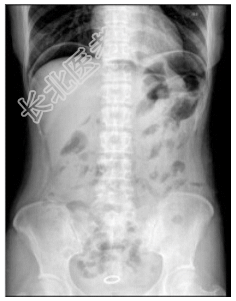

- [材料题] 患者,女性,38岁。突发腹部阵发性疼痛,无恶心、呕吐。查体:全腹轻度压痛,肠鸣音正常。行腹部立卧位片检查。

- 简答题1、患者的诊断及依据是什么?

- 简答题2、鉴别诊断有哪些?